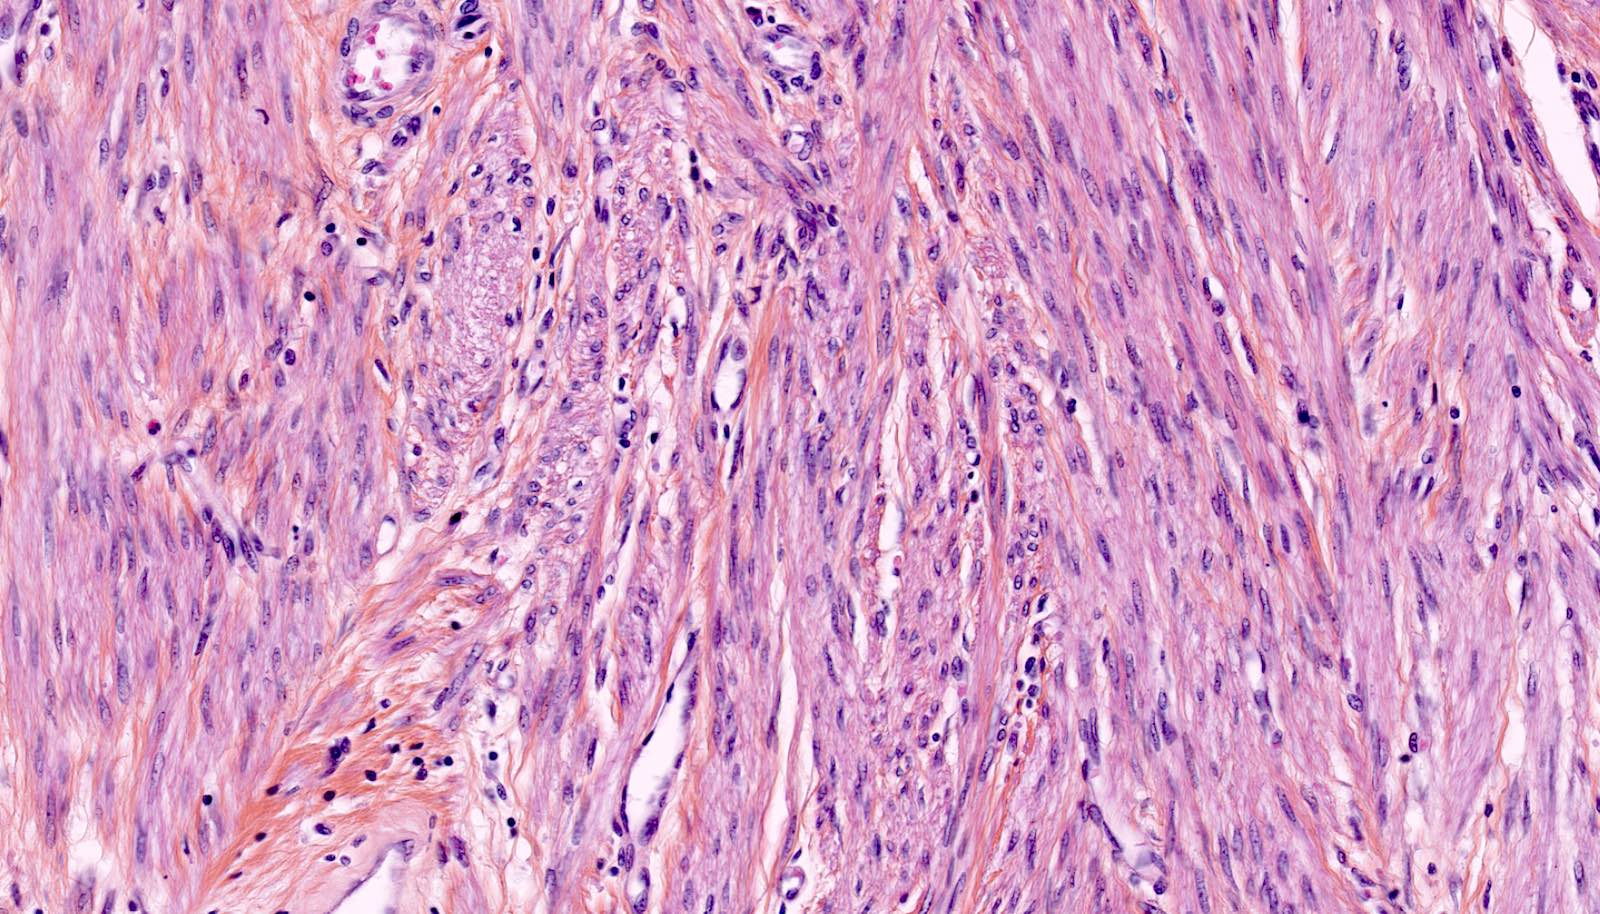

Points of Recognition

- 1Intersecting fascicles of spindle cells

- 2Cigar‑shaped (blunt‑ended) nuclei

- 3Abundant eosinophilic cytoplasm

- 4No nuclear atypia or pleomorphism

- 5Low mitotic count (<5/10 HPF)

- 6Hyaline degeneration (common)

Leiomyoma (fibroid) is the most common benign tumour of the uterus, arising from smooth muscle of the myometrium. Histologically it consists of intersecting fascicles of bland spindle-shaped smooth muscle cells with cigar-shaped nuclei, eosinophilic cytoplasm, and low mitotic activity.

- Intersecting fascicles of spindle-shaped smooth muscle cells

- Elongated cigar-shaped (blunt-ended) nuclei — no significant atypia

- Abundant eosinophilic cytoplasm

- Variable collagen between muscle bundles

- No significant nuclear pleomorphism or hyperchromasia

- Low mitotic activity (<5 mitoses per 10 HPF)